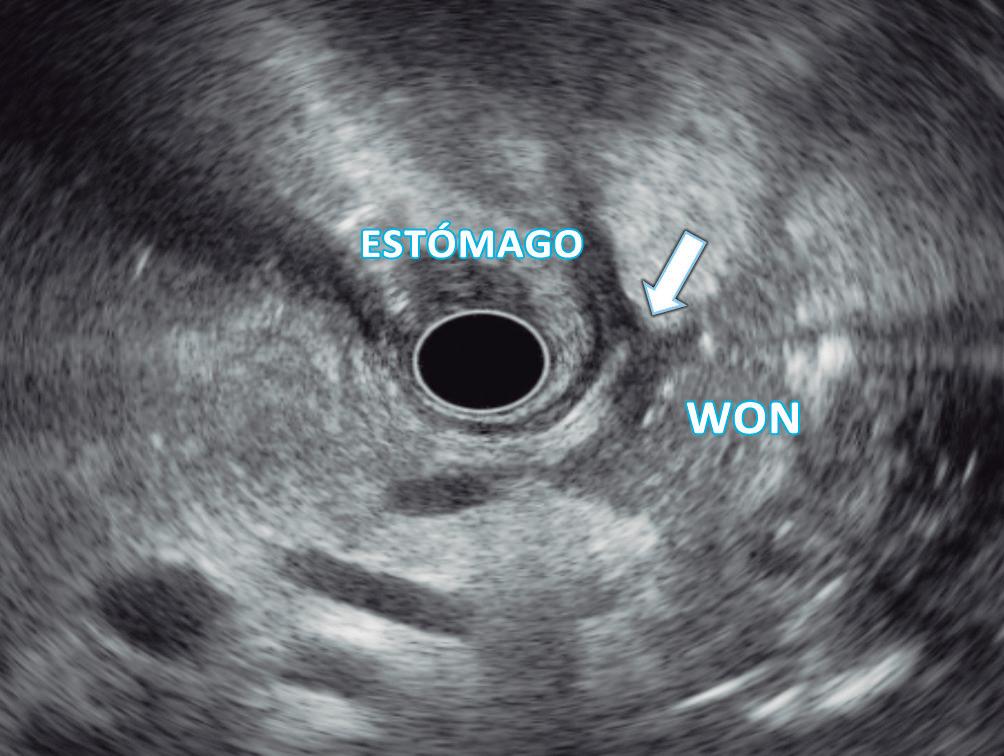

(Figura 1) En los hemangiomas de mayor tamaño el pasaje del contraste al centro de la lesión toma más tiempo e incluso no ocurre en aquellos más voluminosos.

En la RM los hemangiomas son lesiones con señal hipointensa en T1 e hiperintensa muy marcada en T2. Esta última característica los diferencia de otras lesiones benignas o malignas, con excepción de los quistes, que presentan señal más elevada debido a su contenido acuoso.1 El patrón de realce poscontraste es igual al que muestra la TC. (Figura 2) En la secuencia de difusión no presentan un patrón restrictivo, si bien pueden exhibir una señal brillante en valores b altos (parámetro que pondera la difusión); esto se debe al efecto brillo T2 y no a la restricción verdadera, por lo que el mapa del coeficiente de difusión aparente (ADC, por sus siglas en in-

A

glés) muestra señal y valores altos. En estudios con CHE son hipointensos en fase hepatobiliar ya que carecen de hepatocitos. Una potencial causa de error puede ocurrir en algunos hemangiomas pequeños que presenten un refuerzo precoz importante y que en fase de equilibrio (3 minutos) pueden presentarse hipointensos (pseudolavado). De esta manera podrían ser malinterpretados como un CHC.2 No obstante, la característica señal brillante de los hemangiomas en T2 es de utilidad para una tipificación correcta.

A, en fase arterial; B, y en fase de equilibrio; C, que muestran una lesión de contornos lobulados y bordes netos en el lóbulo hepático derecho que presenta refuerzo globular, progresivo e isodenso con las estructuras vasculares.

A: T1 post contraste en fase venosa portal; B, y fase de equilibrio; C: Muestran lesiones en segmentos IV y VI con una señal marcadamente hiperintensa en la secuencia T2 y

Lesiones benignas localizadas en el hígado desde la mirada de las imágenes Mariano Volpacchio Figura 1. Hemangioma en tomografía computada. Imágenes axiales de la TC sin contraste Figura 2. Hemangioma en la RM. Imágenes axiales de la RM en secuencia T2 con supresión grasa con el refuerzo similar a las estructuras vasculares de aspecto globular y progresivo en sucesivas fases. Nótese la heterogeneidad del hemangioma de mayor tamaño en segmento VI. A B C